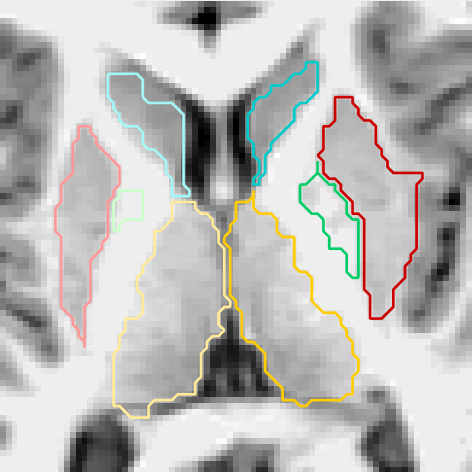

Figures 6 and 3.2 give visual examples of segmentations obtained by our 3D FCNN architecture and standard references contoured by FreeSurfer.

It can be observed that the segmentations generated by our proposed architecture are significantly smoother than those of FreeSurfer, regardless of the subject group (i.e diagnosis, age, site employed or not in training). We also notice that our system is better at identifying thin regions in the structures of interest, for instance, the lower extremities of pallidum (green regions).

Site used in training

FreeSurfer Refer to caption Our CNN Refer to caption Refer to caption Refer to caption

Refer to caption Refer to caption

Figure 6: Visual examples of our 3D FCNN architecture compared with the standard references contoured by FreeSurfer, for three test subjects from sites used in training.